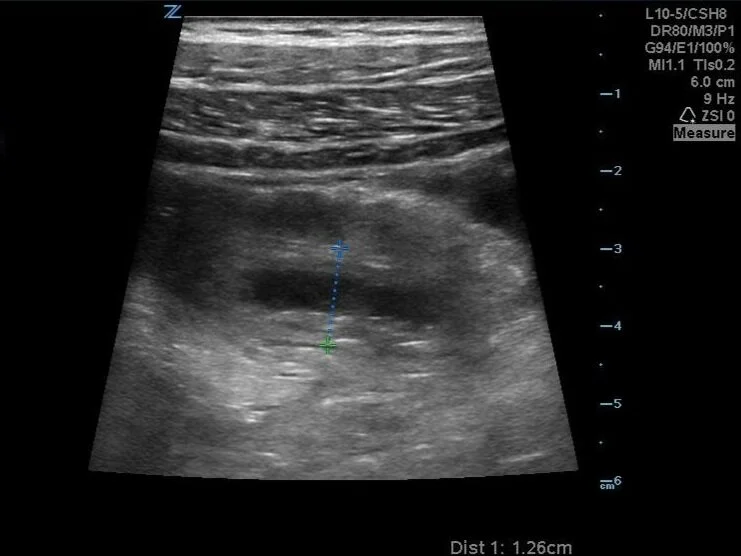

Found something! This fluid filled structure is located well into the RUQ. In fact, that’s the liver just to the left on the screen! As evidenced on this clip, it is not compressible by pressure.

Short axis measurement well over the upper limit of normal for an appendix of 6mm.